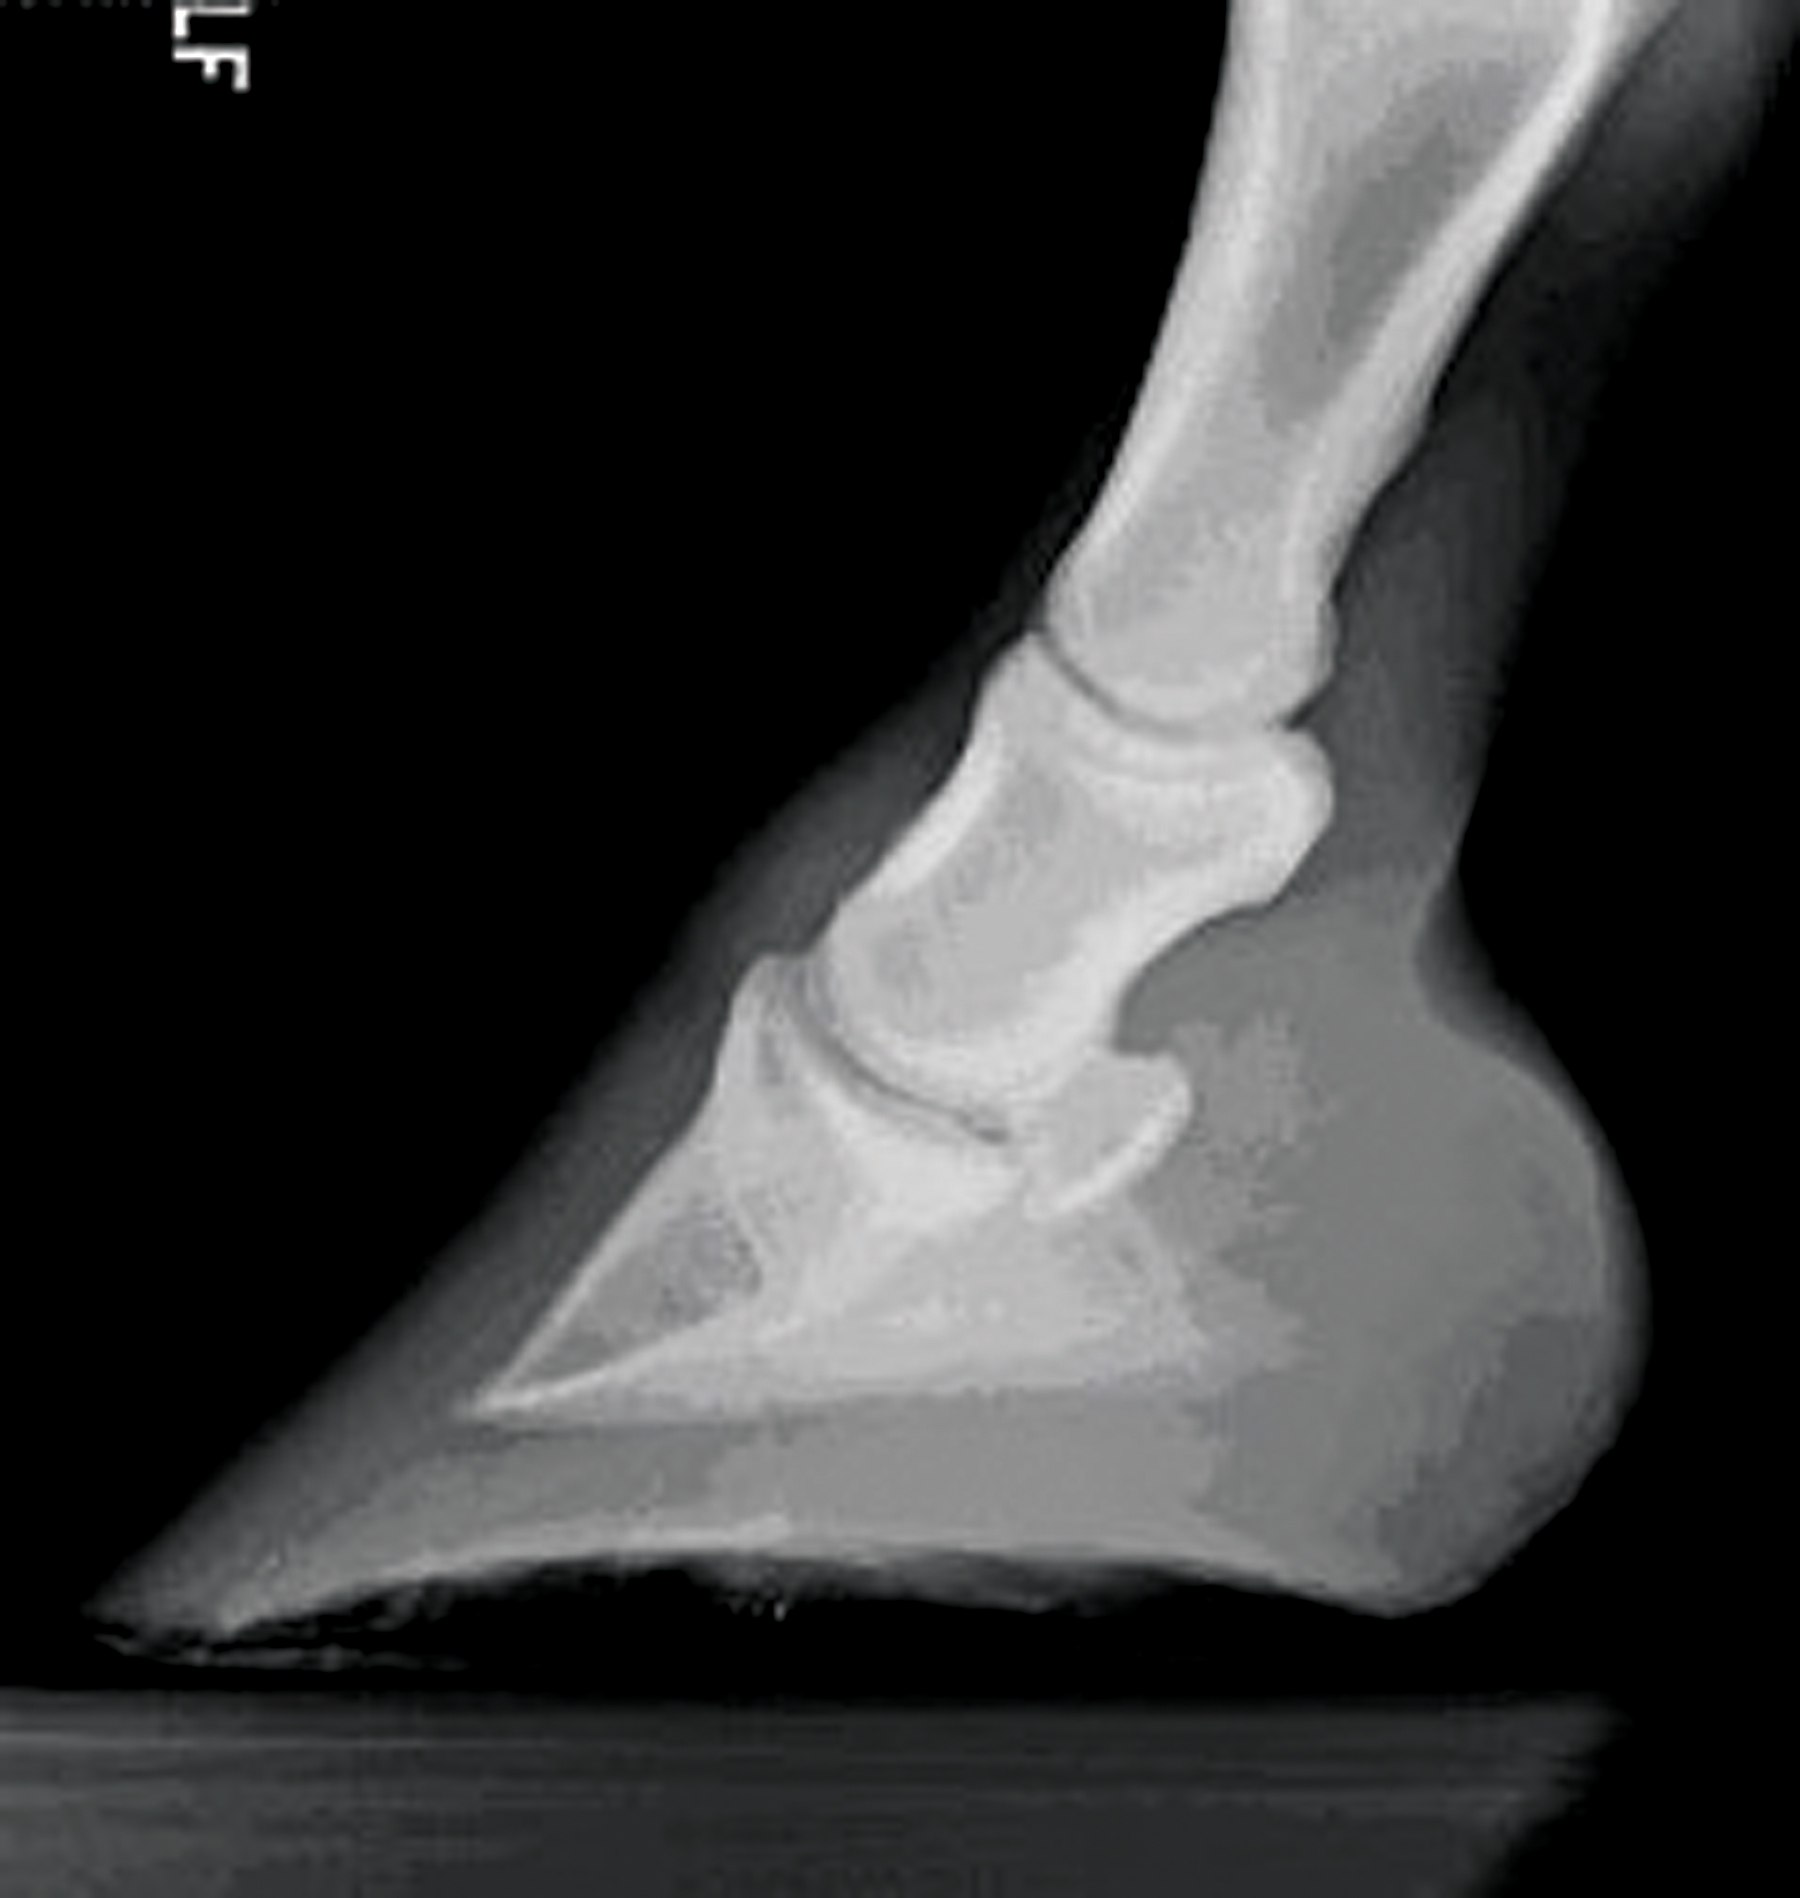

From beckybruce.com

XRays of Laminitis How to Detect Laminitis in Horses Horse Laminitis Episode Causes in horses include carbohydrate overload, excess weight bearing, and endotoxemia. Once a horse has had an episode of laminitis, they are. Laminitis is a crippling condition which can be fatal in severe cases. Laminitis, commonly known as founder, is a painful disease that causes severe lameness in horses. Swelling occurs when the hoof dermis is inflamed and blood circulation. Horse Laminitis Episode.